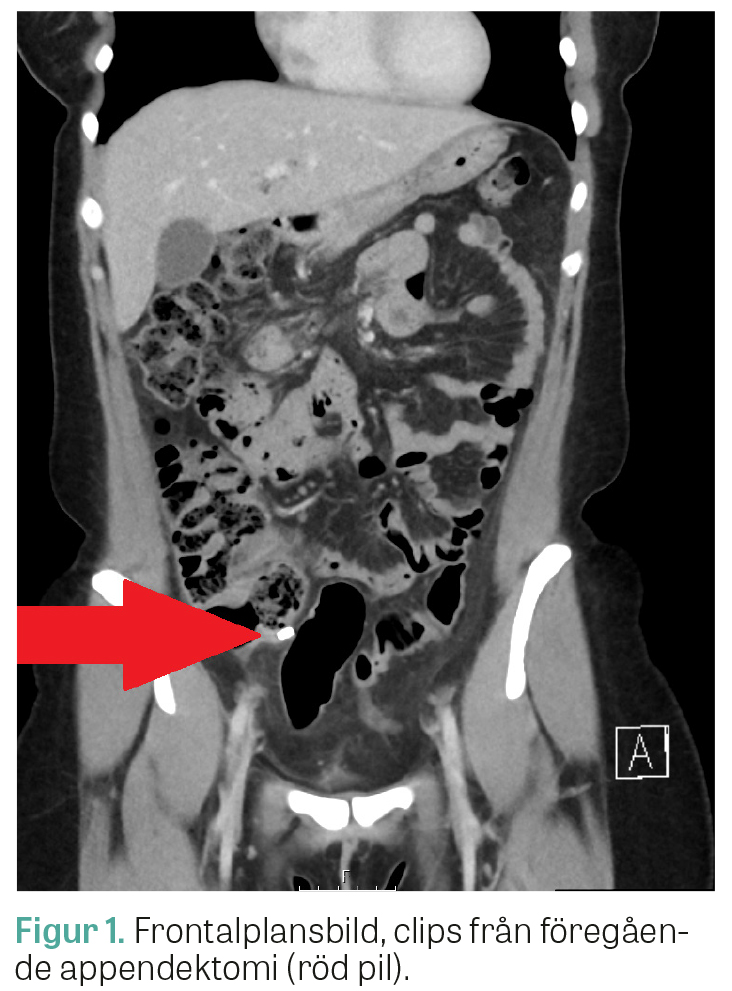

2 dagar senare sökte patienten till en akutmottagning med förvärrade smärtor som hade blivit tydligare lokaliserade till höger i nedre delen av buken. Patienten hade fortsatt NEWS 0 poäng. CRP hade däremot stigit till 38 mg/l. LPK var 11 × 109/l. Buken palperades med lokal peritonit i höger fossa. Akutläkaren remitterade patienten till en akut gynekologisk undersökning. Bedömningen var att patienten inte hade någon påvisbar gynekologisk åkomma, och symtombilden tolkades som en kirurgisk buk. En datortomografi av buken beställdes, och patienten återvände efter denna till akutmottagningen. Datortomografin visade clips från tidigare appendektomi (Figur 1), men även lokal retning i fettvävnaden kring en retrocekal struktur som tedde sig tubulär och väggförtjockad, och radio­logen väckte frågan om abscess, alternativt stumpappendicit (Figur 2). Tanken att det kunde röra sig om en appendixduplikatur väcktes också. Kvinnan lades in fastande med smärtlindring och uppvätskning på en kirurgisk avdelning. De kommande dagarna förbättrades hon kliniskt och laboratoriemässigt. Fallet drogs efter 2 dagar på kirurgklinikens konferens med bildgranskning, och diagnosen appendixduplikatur ställdes baserat på sammanställning av radiologisk och klinisk bedömning samt klinskt förlopp. Patologisk-anatomisk diagnos (PAD) kan inte användas för att säkerställa diagnosen om patienten behandlas konservativt, men eftersom patienten var kliniskt återställd gjordes bedömningen att hon kunde skrivas hem under aktiv exspektans. Patienten informerades om att hon har en appendix­duplikatur som sitter retrocekalt och som bör uppmärksammas vid framtida kontakt med vården.